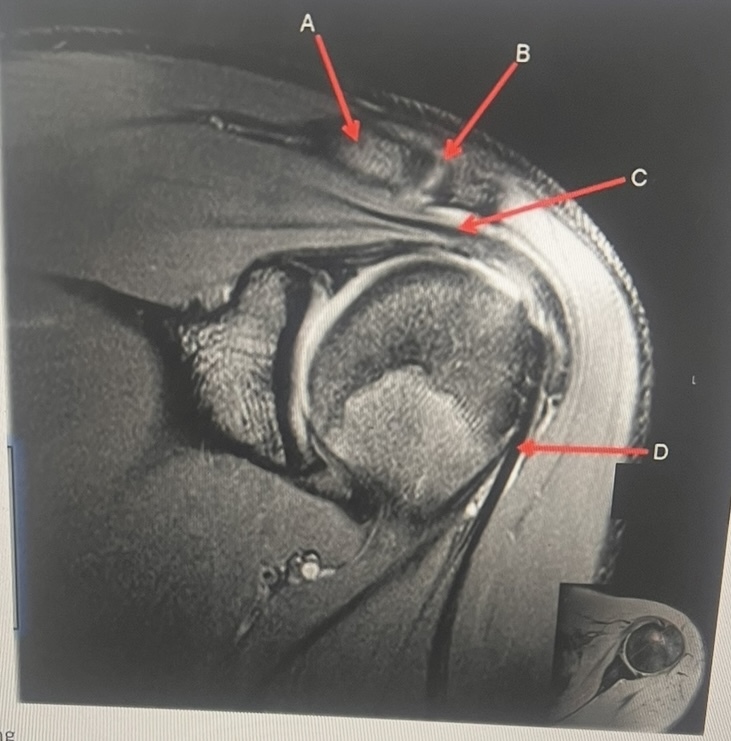

18

Q

clavicle, AC joint, supraspinatus tendon, biceps tendon

A

A. clavicle

B. AC joint

C. supraspinatus tendon

D. biceps tendon

Shoulder imaging is acquired with oblique acquisition. How are coronal oblique images prescribed? A. Parallel to the supraspinatus tendon B. Parallel to the glenoid fossa C. perpendicular to scapular spine D. Along the subscapularis muscle E. A or B

A. Parallel to the supraspinatus tendon

What do you cover while scanning a shoulder in axial plane? A. Superior Iabrum to inferior labrum. B. supraspinatus tendon down to glenoid process C. AC joint to inferior labrum

C. AC joint to inferior labrum